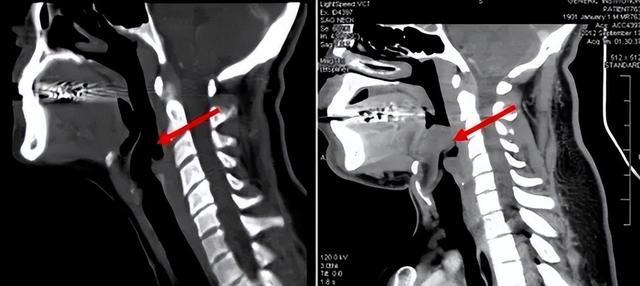

会厌,位于气管的上方,这个部位可以随着吞咽的动作而进行上下扇动。

这么说可能很难理解,直白点说,当人在吃饭吞咽时,会厌会像盖子一样盖住咽喉入口,防止食物进入喉腔或气管引起呛咳;而人在呼吸时,会厌又会向上开放,以保证气流能顺利进入气管。

会厌一旦发炎,就会不断肿胀,严重时可能会肿胀成球状,这时气道便会封闭,人也就无法呼吸。